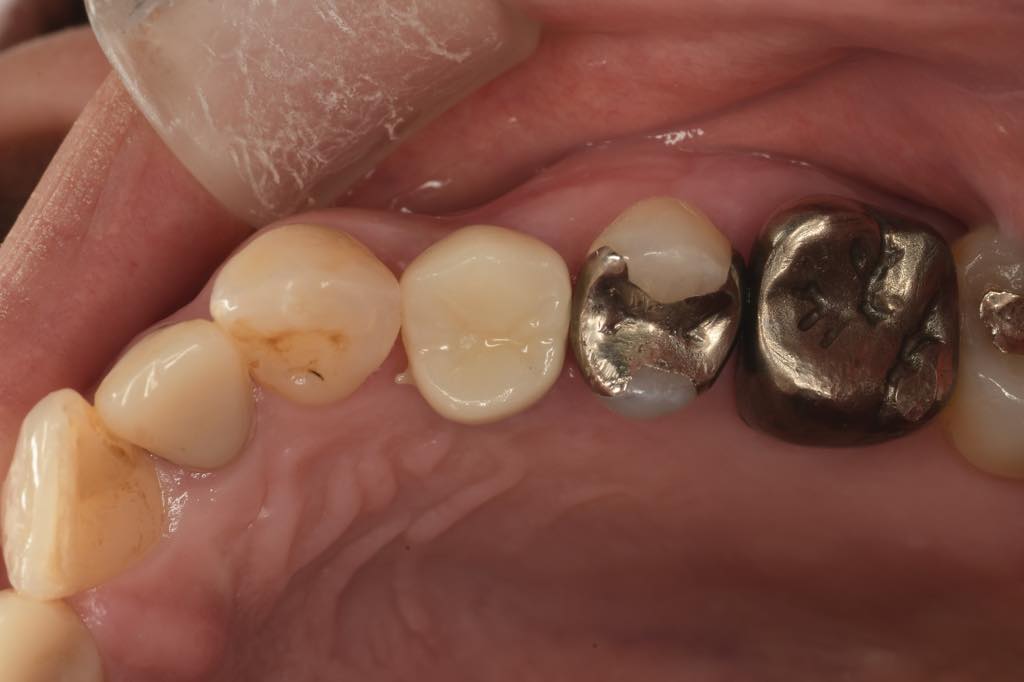

CASE 01

| 主訴 | 歯が割れた |

| 治療内容 | 左下6番 インプラント治療(骨の再生療法含む) |

| 治療回数 | 14回 |

| 治療費用 | ¥460,000 |

| 想定される副作用 | 腫れ、痛み |